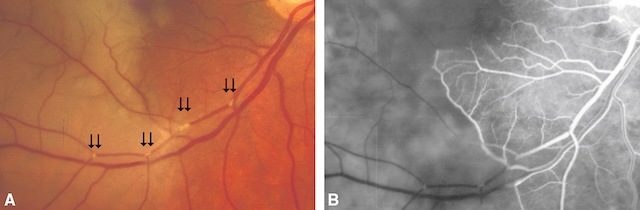

Dans les tout premiers instants, la rétine peut avoir encore un aspect normal, mais il existe un rétrécissement diffus du calibre artériel et parfois un courant granuleux qui est plus facile à voir sur l’angiographie à la fluorescéine. Dans les heures qui suivent, un œdème ischémique rétinien, blanchâtre apparaît. Il traduit la souffrance ischémique des couches internes de la rétine. La fovéola, qui n’est pas masquée par l’œdème de la rétine interne, garde sa coloration normale et apparaît plus rouge par contraste avec tout le reste de la rétine ischémique (« tache rouge cerise de la macula »; fig. 16.7A).

A. Cliché du fond d’œil. Rétine de coloration blanchâtre, sauf au niveau de la fovéola (tache rouge cerise de la macula). B-D. Angiographie fluorescéinique du fond d’œil : retard extrême de remplissage des branches de l’artère centrale de la rétine (B, C) avec courant granuleux, et allongement du temps de passage artérioveineux (D : il n’existe encore qu’un début de remplissage veineux plus de 6 minutes après l’injection de fluorescéine).

Cette série d’images montre les différentes phases d’exploration d’une occlusion de l’artère centrale de la rétine. En A, le fond d’œil couleur révèle un œdème rétinien pâle avec un macula en cerise centrale, reflet d’une ischémie aiguë. L’image B en angiographie précoce montre un retard net de remplissage artériel. L’image C confirme une absence de perfusion artérielle centrale, tandis que D met en évidence la persistance d’une perfusion veineuse périphérique partielle, contrastant avec la zone centrale sombre. L’ensemble illustre une ischémie rétinienne sévère avec atteinte du flux artériel principal.

L’angiographie à la fluorescéine est marquée par :

- •

un retard extrême de perfusion des branches de l’artère centrale de la rétine (fig. 16.7B,C); -

le temps bras rétine normal est inférieur à 15 secondes (durée entre le moment d’injection de la fluorescéine au pli du coude et son arrivée dans l’artère centrale). Dans l’OACR, il peut atteindre plusieurs minutes; - •

un allongement du temps de passage artérioveineux rétinien

(temps entre l’arrivée de la fluorescéine dans l’artère centrale, son passage dans les capillaires et le retour veineux) qui normalement est inférieur à 3 secondes (fig. 16.3D).